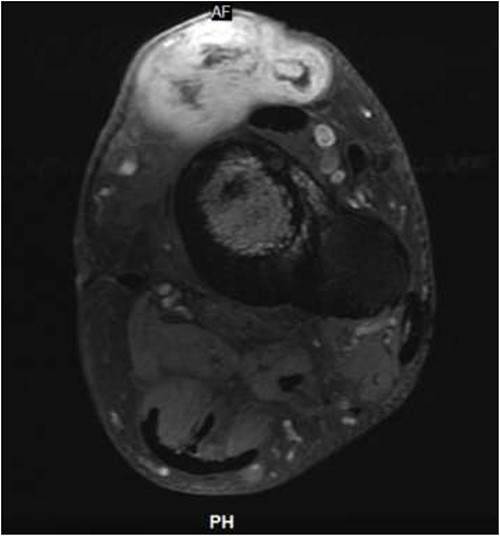

He presented upon noticing a lump overlying the rectus flap. On exam, the left lower extremity had multiple incisions with well-healed scars and a protruding lesion at the distal aspect of his previous incision, which was non-tender to palpation (Fig. 1). MRI of the lower extremity revealed a soft tissue mass in the anterior compartment of the left lower extremity (Figs 2 and 3). Biopsy of the lesion demonstrated RMS and molecular diagnostics revealed missense mutations in MYOD1 (p.L122R) and DOT1L (p.G1441R). Tumor cells were microsatellite stable. The copy number profile is suggestive of broad copy number gain of chromosome 5p. The patient was discussed at the local tumor board and was treated with D9803 chemo protocol (vincristine-based), receiving 4 cycles before proceeding to operative management.

Surgical pathology confirmed rhabdomyosarcoma, high-grade spindle cell sclerosing type, measuring 4.0 × 3.0 × 2.8 cm. Mitotic rate was 7/10 per HPF, and areas of fibrosis were consistent with chemotherapeutic response. Margins were negative for tumor, and the tumor was 1 mm from the deep margin. Lympho-vascular invasion was not identified.